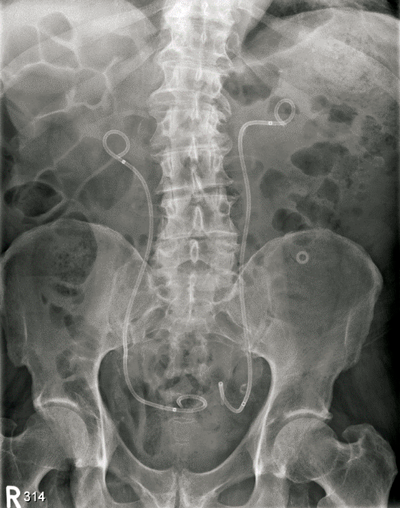

A 76-year-old male with end stage renal failure due to obstructive uropathy from benign prostatic enlargement was transferred from a referring hospital. A right ureteric stent had been placed and a left sided stent was sited too far proximally in the ureter (Figure 1). Comorbidity included ischaemic heart disease, cardiac failure and the patient was anti-coagulated. There had been one failed attempt to re-position the stent.

Figure 1.